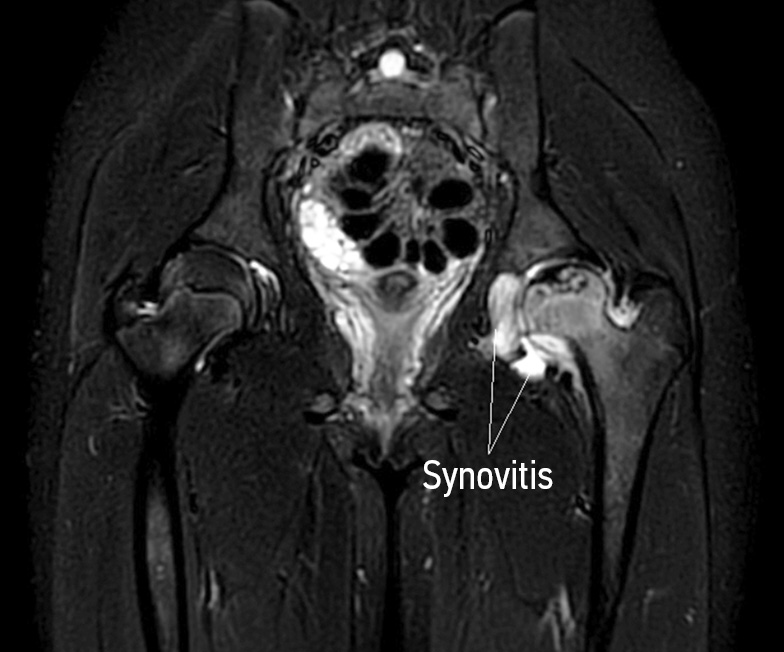

Currently, the treatment of osteoarthritis in the presence of LCPD represents an unsolved problem in pediatric rheumatic orthopedics. Most pediatric rheumatologists interpret the inflammatory process against aseptic necrosis as synovitis of a secondary nature, the absence of factors of autoimmune aggression, which excludes the possibility of using antirheumatic drugs [30]. Moreover, despite the seemingly chronic nature of the course, synovitis, combined with aseptic necrosis, does not fit into any of the criteria for rheumatic disease. This predetermines the impossibility of using immunosuppressive therapy in this category of patients. In this case, the inflammatory process in the joint persisting for at least 6 weeks in a child with avascular necrosis cannot but be associated with the course of the disease. This form of inflammation, emanating from the focus of necrosis, leading to the onset and progression of femoral head deformity, and affecting the cartilaginous model, should be interpreted as osteoarthritis [31]. Undoubtedly, suppression of this inflammatory process is required (Fig. 3). Therapy with nonsteroidal anti-inflammatory drugs is often insufficient and does not help to subside the inflammatory changes. That is why it is necessary to strengthen anti-inflammatory therapy using immunosuppressive drugs. However, using algorithms and regimens of immunosuppressive therapy with the inclusion of antirheumatic disease-modifying drugs is not the responsibility of the orthopedic physician. In addition, the orthopedist needs the necessary skills to assess the efficiency and safety of immunosuppressive therapy in pediatric patients. This clearly demonstrates the unresolved problem of treating chronic synovitis in pediatric patients with LCPD and necessitates involving a rheumatologist. At the same time, despite the disease’s multifactorial nature, several pathogenetic mechanisms still have clearly described aspects. Numerous studies have shown the leading role of uncontrolled activation of osteoclasts in the formation of ANFH, accompanied by overproduction of proinflammatory cytokines and the development of chronic synovitis [32]. Such a reaction of the synovial membrane is not unfounded and can be associated with hidden mechanisms of autoaggression. Therefore, a selective model for the treatment of chronic synovitis in pediatric patients with LCPD may not have a direct immunosuppressive effect on inflammation but an indirect one by blocking osteoclast hyperactivity [33].

Fig. 3. Magnetic resonance imaging shows stage 2 of osteochondropathy of the femoral head on the left with signs of osteoarthritis (from the author’s archive). Magnetic resonance imaging in T2 STIR modes reveals an extensive area of femoral head destruction, signs of trabecular edema, and chronic synovitis